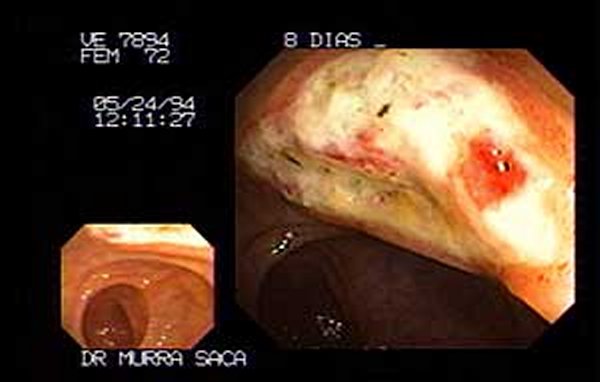

FOTOGRAFIA DE UNO DE LOS POLIPOS MÁS GRANDES QUE HEMOS EXTRAIDO EN UN SOLO TIEMPO, MIDIO 6CM X 2.8CM. LA MAYORIA DE POLIPOS DE GRAN TAMAÑO LOS EXTRAEMOS CON LA TECNICA DE REBANADAS.-

Ver abajo las secuencias de esta extracción de uno de los tumores más grandes que hemos extraído por medio de los equipos de colonoscopia. (Sólo uno ha sido más grande que éste pero fue extraído por rebanadas en varias secciones diferentes).

Paciente femenina de setenta y dos años quien consulta por hemorroides.

Efectivamente tenia hemorroides, pero en el tacto rectal le encontramos este tumor de gran tamaño, adenoma velloso con células displásicas en el área rectal antes de la primera válvula.

Después de haber obtenido el resultado de la biopsia se procede a extraerlo por medio de la colonoscopia.

El tumor se ha desprendido dejando una ulceración que cicatriza sola.

Ulceración post polipectomía endoscópica de tumor precanceroso de gran tamaño.

La ulceración en fase de cicatrización ocho días después de la resección transendoscópica. El tejido granula en forma gradual, la fibrina está organizada en un promedio de dos semanas. Cicatriza completamente. El paciente se beneficia al no tener una cirugía abierta. Y lo más importante es salvarse de un cáncer. Este tumor precanceroso no se formó en un día, estos tipos de tumores pasan años en crecer y la única forma de detectarlos es por medio de los exámenes que practicamos a diario. No se deje ser sorprendido por un cáncer. Revise su cuerpo el cáncer en sus inicios (varios años no da síntomas)